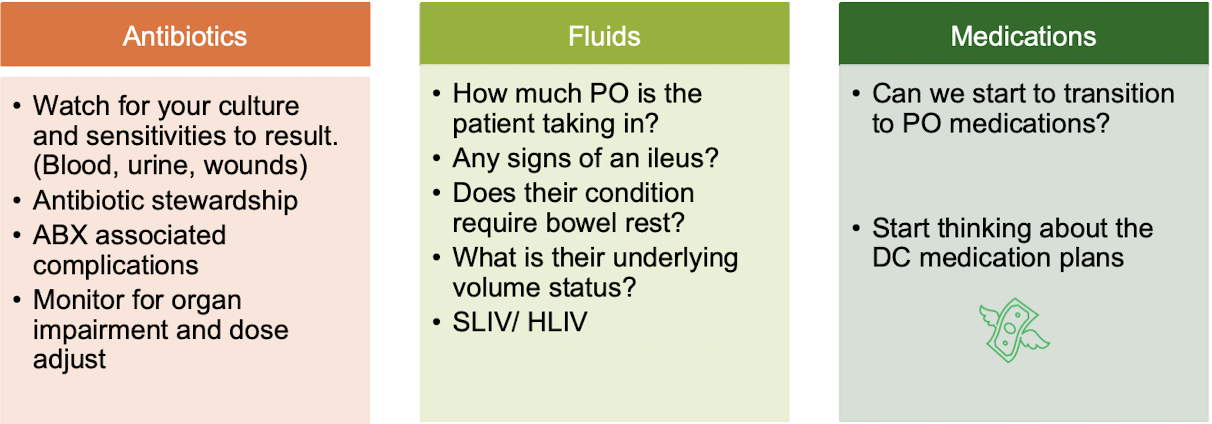

Indwelling catheters

all _____ should be carefully monitored for time of placement and removal indications

-remove lines within guidelines and caution for infections

*CLABSI (Central Line-Associated Bloodstream Infection) and

CAUTI (Catheter-Associated Urinary Tract Infection) are leading causes of Hospital-Associated Infection

FASTHUGSBID - ___________

Deescalation

FASTHUGSBID - ___________

Medication Reconciliation

-review with patient and family the name, dosage, frequency, timing, and duration of all medications patient is taking at home; check allergies and intolerances